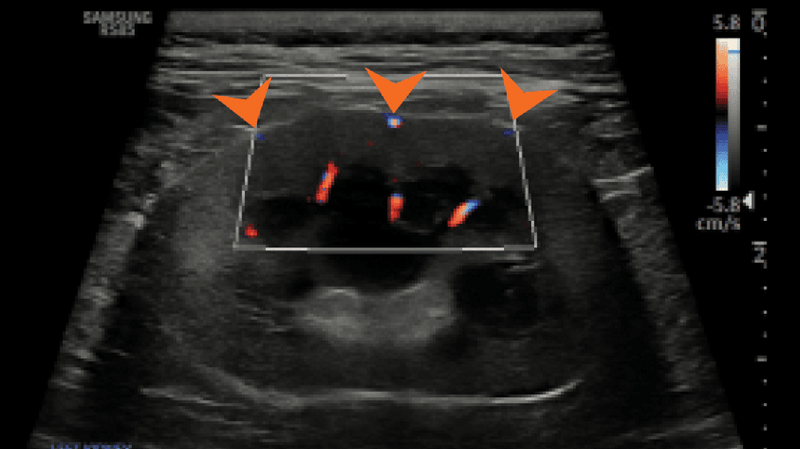

Prawidłowy obraz ultrasonograficzny nerek został szczegółowo omówiony w innych źródłach,7 a poniższy artykuł koncentruje się na przewlekłej chorobie nerek u kotów i psów. Nerki powinny być obrazowane w trzech projekcjach – strzałkowej, dogrzbietowej i poprzecznej (ryc. 1).7 U psów, zwłaszcza małych ras, opisano obecność hiperechogenicznego zewnętrznego pasma rdzeniowego, które obserwuje się z umiarkowaną częstością u pacjentów bez stwierdzonej choroby nerek (ryc. 2).8 U kotów kora nerek może być jednorodnie silnie hiperechogeniczna ze zwiększonym w następstwie zróżnicowaniem korowo-rdzeniowym wtórnym do lipidozy kanalików bliższych (ryc. 3).9 Odkładanie się tłuszczu w kanalikach nerkowych jest konsekwencją otyłości bez jednoczesnego upośledzenia czynności nerek.10 Dodatkowo rutynowo obserwuje się zależny od kąta badania artefaktowy wzrost hiperechogeniczności kory i rdzenia nerek, wtórny do anizotropii, w obszarach, w których kanaliki nerkowe ułożone są prostopadle do płaszczyzny fali ultradźwiękowej. Na przykład podczas obrazowania nerki w projekcji strzałkowej echogeniczność biegunów doczaszkowego i doogonowego będzie ogniskowo i artefaktowo zwiększona (ryc. 4).11 Z doświadczenia autorów wynika, że łagodna nieregularność brzegów nerek, szczególnie u kotów, może być obserwowana w miejscach, gdzie naczynia nerkowe przebiegają wzdłuż torebki nerkowej, i nie powinna być błędnie interpretowana jako zmiana zwyrodnieniowa (ryc. 5). W lokalizowaniu tych naczyń użyteczna jest ultrasonografia dopplerowska kodowana kolorem lub w trybie mocy.

Medium huguet ryc5 opt

Ryc. 5. Badanie ultrasonograficzne metodą dopplera mocy lewej nerki kota, ukazujące równomiernie nieregularne brzegi w miejscach, gdzie naczynia nerkowe przebiegają wzdłuż torebki nerki (groty strzałek).